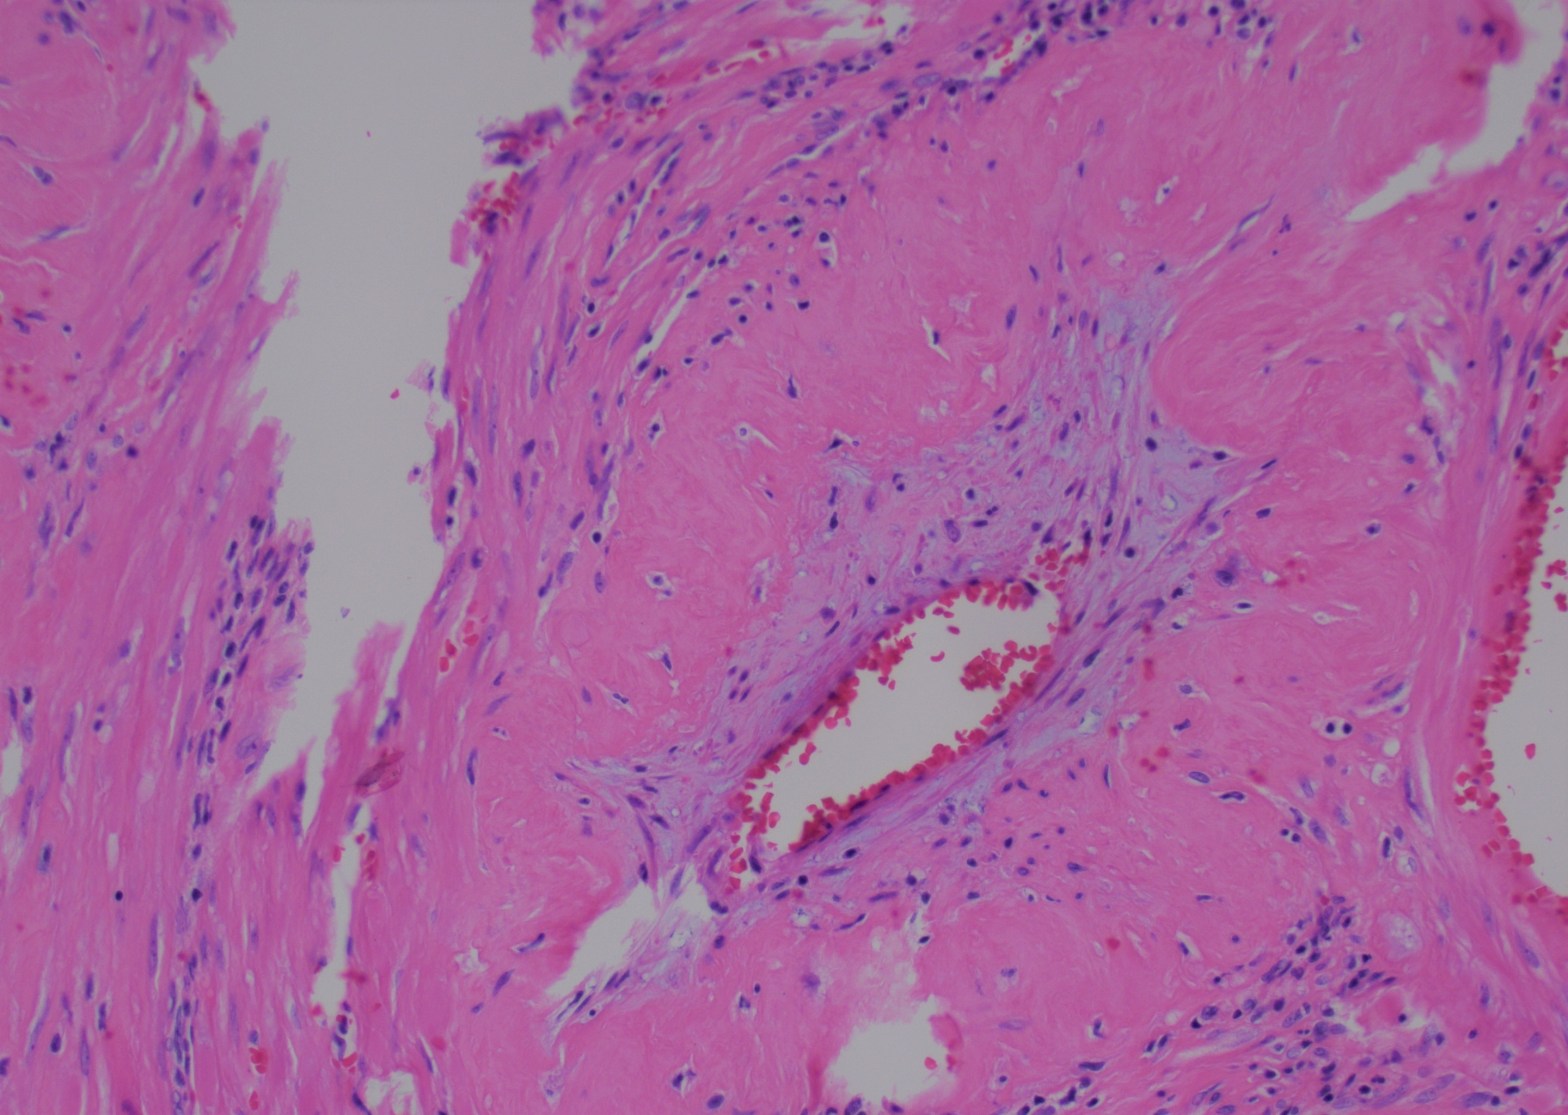

Delayed Postpartum Haemorrhage

Postpartum hemorrhage can be seen immediately after delivery or it can be delayed and may appear weeks or even months after delivery. Common reasons for postpartum hemorrhage are injury of the cervix or uterus, uterine atony, retained placental tissue, endometritis, placenta accreta. Delayed postpartum hemorrhage is likely to be associated with a pathologic process andContinue reading “Delayed Postpartum Haemorrhage”